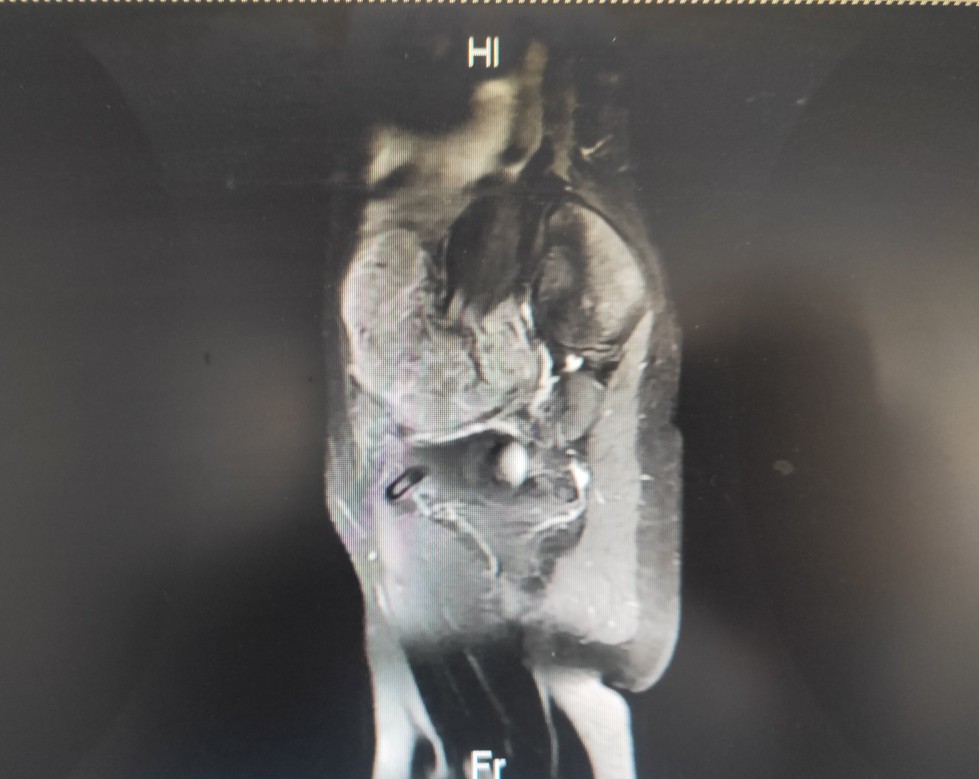

一位22岁的年轻女性,于2020年2月初诉下腹部隐痛,伴腹胀,乏力,就诊门诊妇科,查体发现左下腹一质硬包块,行盆腔核磁共振示:盆腔及子宫腔内多发占位。便收入院治疗,入院做上腹部CT示:肝脏多发低密度占位,考虑转移性病变。

入院后行手术治疗,术后病理:子宫内膜样癌,FⅠGOII级,侵及子宫壁全层,脉管内癌栓,双侧卵巢,左右宫旁,大网膜见癌累及。目前分期晚,预后差,需行术后辅助治疗。